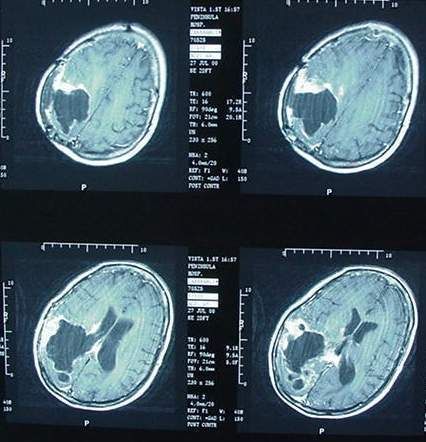

Il y a également un lien évident aujourd'hui entre la multiplication des réseaux mobiles, l'utilisation massive et intensive des technologies mobiles et la recrudescence de cancer cérébral.

Le 31 mai 2011, le Centre international de recherche sur le cancer (Circ) à Lyon, organisme de l'Organisation mondiale de la santé, classait comme "peut-être cancérogène pour l'homme" (2B) les champs électromagnétiques de radiofréquences, autrement dit les ondes émises par les téléphones mobiles, les experts se sont basés sur une étude montrant un risque de gliome accru de 40% chez des "gros" utilisateurs de téléphone portable (30 minutes/ jour en moyenne sur 10 ans).